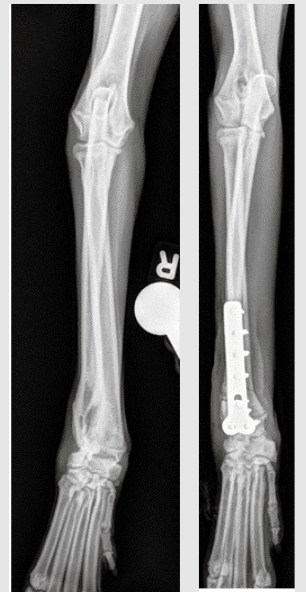

The two x rays below below are an example of Dr. Sam Franklin’s patient. This bow-legged dog’s appearance was due to a relatively simple deformity of the right forelimb that was characterized with radiography (i.e. X-ray), fixed with a bone plate in screws, and had an excellent outcome.